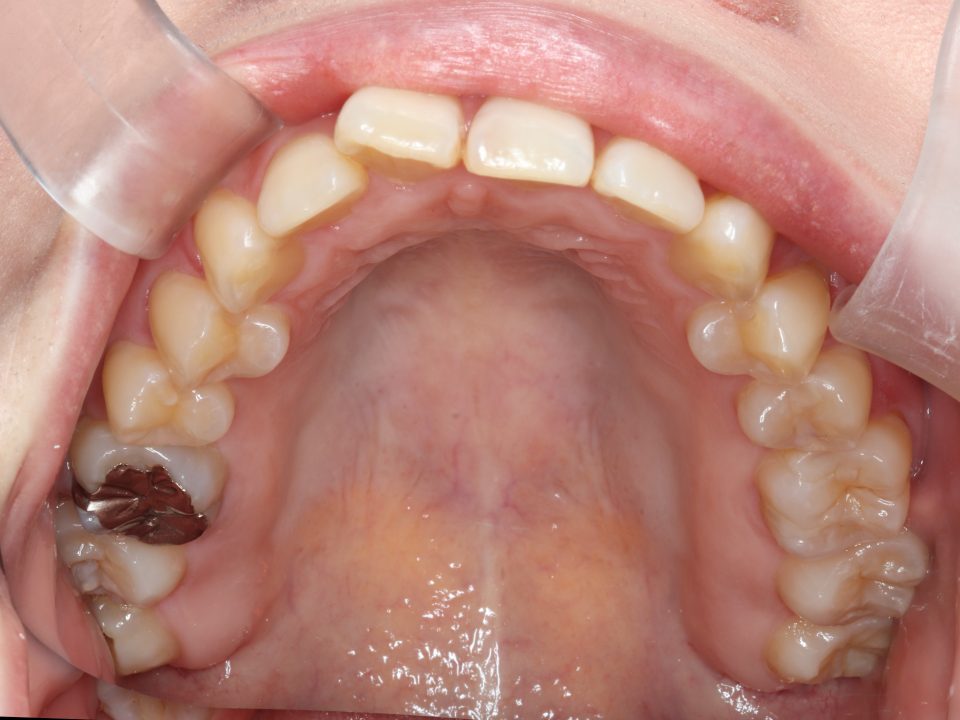

矯正治療前

部分的な矯正治療を希望され、

マウスピース型の矯正治療装置を使用し、歯のやすり掛け(IPR)を行いました。